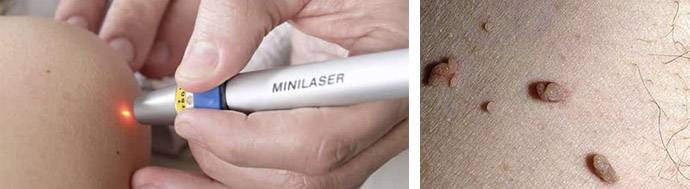

Методы удаления

Фото: метод криодеструкции

- Радиоволновое удаление. Это хирургическая техника, в основе которой лежит разрушение клеток под воздействием волны. Процесс длится около 5-10 минут. После операции в большинстве случаев не наблюдается осложнений. Для удаления папиллом в чувствительных местах перед радиоволновым методом проводится анестезия.

- Криотерапия. Нарост прижигают жидким азотом. Пациент ощущает легкое жжение и холод. Через некоторое время после процедуры папиллома отпадает. Преимущество метода заключается в его безболезненности, а также в отсутствии рубцов после удаления.

- Электрокоагуляция. В основе лежит использование электрического высокочастотного тока. На поверхность папилломы и участка вокруг нее накладывается проводящий электрод. Далее пораженное место обрабатывают диатермическим ножом, в результате чего происходит мощное выделение теплоэнергии, и сосуды разрушаются. Процедура проходит быстро и безболезненно, а ранка заживает через несколько дней.